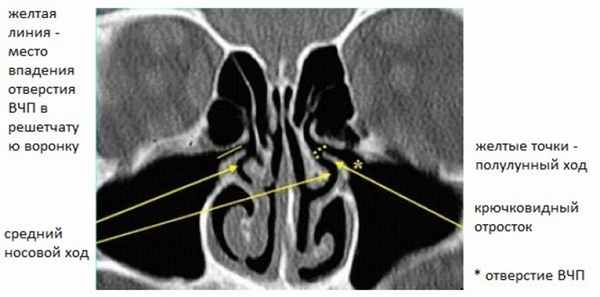

Рисунок 1. КТ полости носа. Нормальный передний остиомеатальный комплекс Хорошо видна анатомия решетчатой воронки и крючковидного отростка.

Крючковидный отросток (КО) и латеральная стенка полости носа формируют решетчатую воронку (РВ). Вышеуказанные пазухи дренируются в РВ через разные отверстия. Отверстие верхнечелюстной пазухи (ВЧП) и карман (или проток) лобной пазухи (ЛП) (см. Рис. 2) открываются в самую переднюю часть ОМК, хорошо и постоянно видны на КТ сканах.

Рисунок 2. КТ полости носа. Лобная пазуха открывается в средний носовой ход сразу латерально от передней части средней носовой раковины. Самые передние решетчатые ячейки называются «агаровые ячейки носа».

Другие отверстия формируются из передних и средних групп решетчатых ячеек и тоже открываются в РВ, но не видны даже на 2 мм фронтальных КТ. Когда в процесс вовлечены лобные, верхнечелюстные пазухи, а также передние и средние ячейки решетчатых лабиринтов, такой паттерн называется инфундибулярным паттерном. Данный паттерн наиболее часто встречается при хроническом синусите.